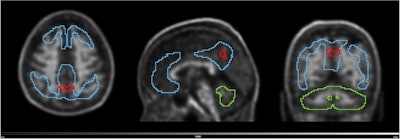

Volume with higher baseline signal for N1 accumulators and N1 non-accumulators of amyloid (red line) overlayed on the scan of an N1 accumulator (MNI space). Grey scale shows SUVR range. Blue line shows the Centiloid target region and the green line shows the reference region (whole cerebellum). Image and caption available for republishing under Creative Commons license (CC BY 4.0 DEED, Attribution 4.0 International) and courtesy of the European Journal of Nuclear Medicine and Molecular Imaging.

Finally, in a parametric image analysis of N1 accumulators, a region within the precuneus was linked to increased amyloid over time, the researchers reported.

Nonetheless, the study also validates that the precuneus is a cortical region with early amyloid accumulation in Alzheimer’s disease and that its focal signal can lead to positive visual PET reads on images from patients with low CL values, the group added.